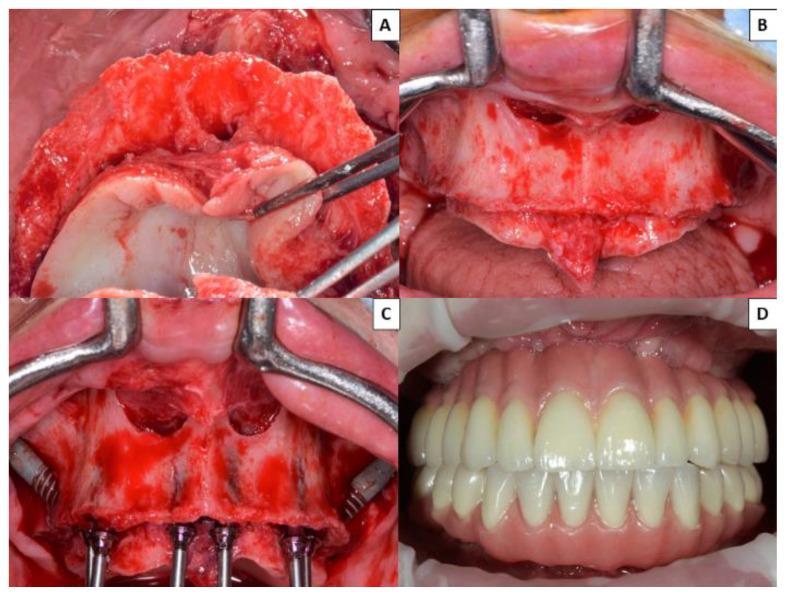

: No published research has compared patients' quality of life and satisfaction with fixed prostheses supported by zygomatic implants with those supported by all-on-four prostheses. The aim of this study was to evaluate patients' quality of life and satisfaction with fixed prostheses on zygomatic implants compared with the all-on-four concept. : A total of 80 patients with atrophic edentulous maxillae were randomized into two groups: Group 1 (rehabilitated with fixed prostheses supported by 2-4 zygomatic and 2-4 conventional implants in the anterior region) and Group 2 (fixed prostheses on four implants in the anterior region following an all-on-four concept). One year after placement of the definitive prostheses, patients completed OHIP-14 and satisfaction questionnaires. : In all seven domains of the OHIP-14 and in the overall scores, a worse quality of life was found in Group 2 patients, with statistically significant differences between the two groups ( ≤ 0.05). Patients with zygomatic implants were more satisfied with their prostheses, with a statistically significant difference ( < 0.001). : According to the results of this study, rehabilitation of patients with edentulous atrophic maxillae with prostheses supported by zygomatic implants combined with anterior implants provided better patient quality of life and satisfaction than prostheses supported by four implants.